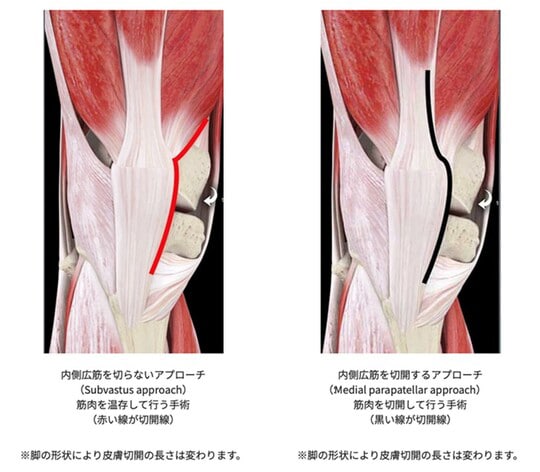

たとえば、通常は内側広筋(ないそくこうきん)を切開して行う方法が一般的ですが、筆者は皮膚の切開を最小限に抑え、さらに内側広筋を切らずにアプローチするという、筋肉を温存する術式を採用しています。

手術ではその点も考慮し、術後の速やかな回復をサポートするため、極力低侵襲の術式を採用することが大切です。下記のレントゲンを見ると分かるように、Aさんの手術は無事成功しました。